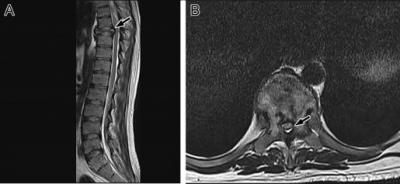

Diagnosis of Langerhans cell sarcoma